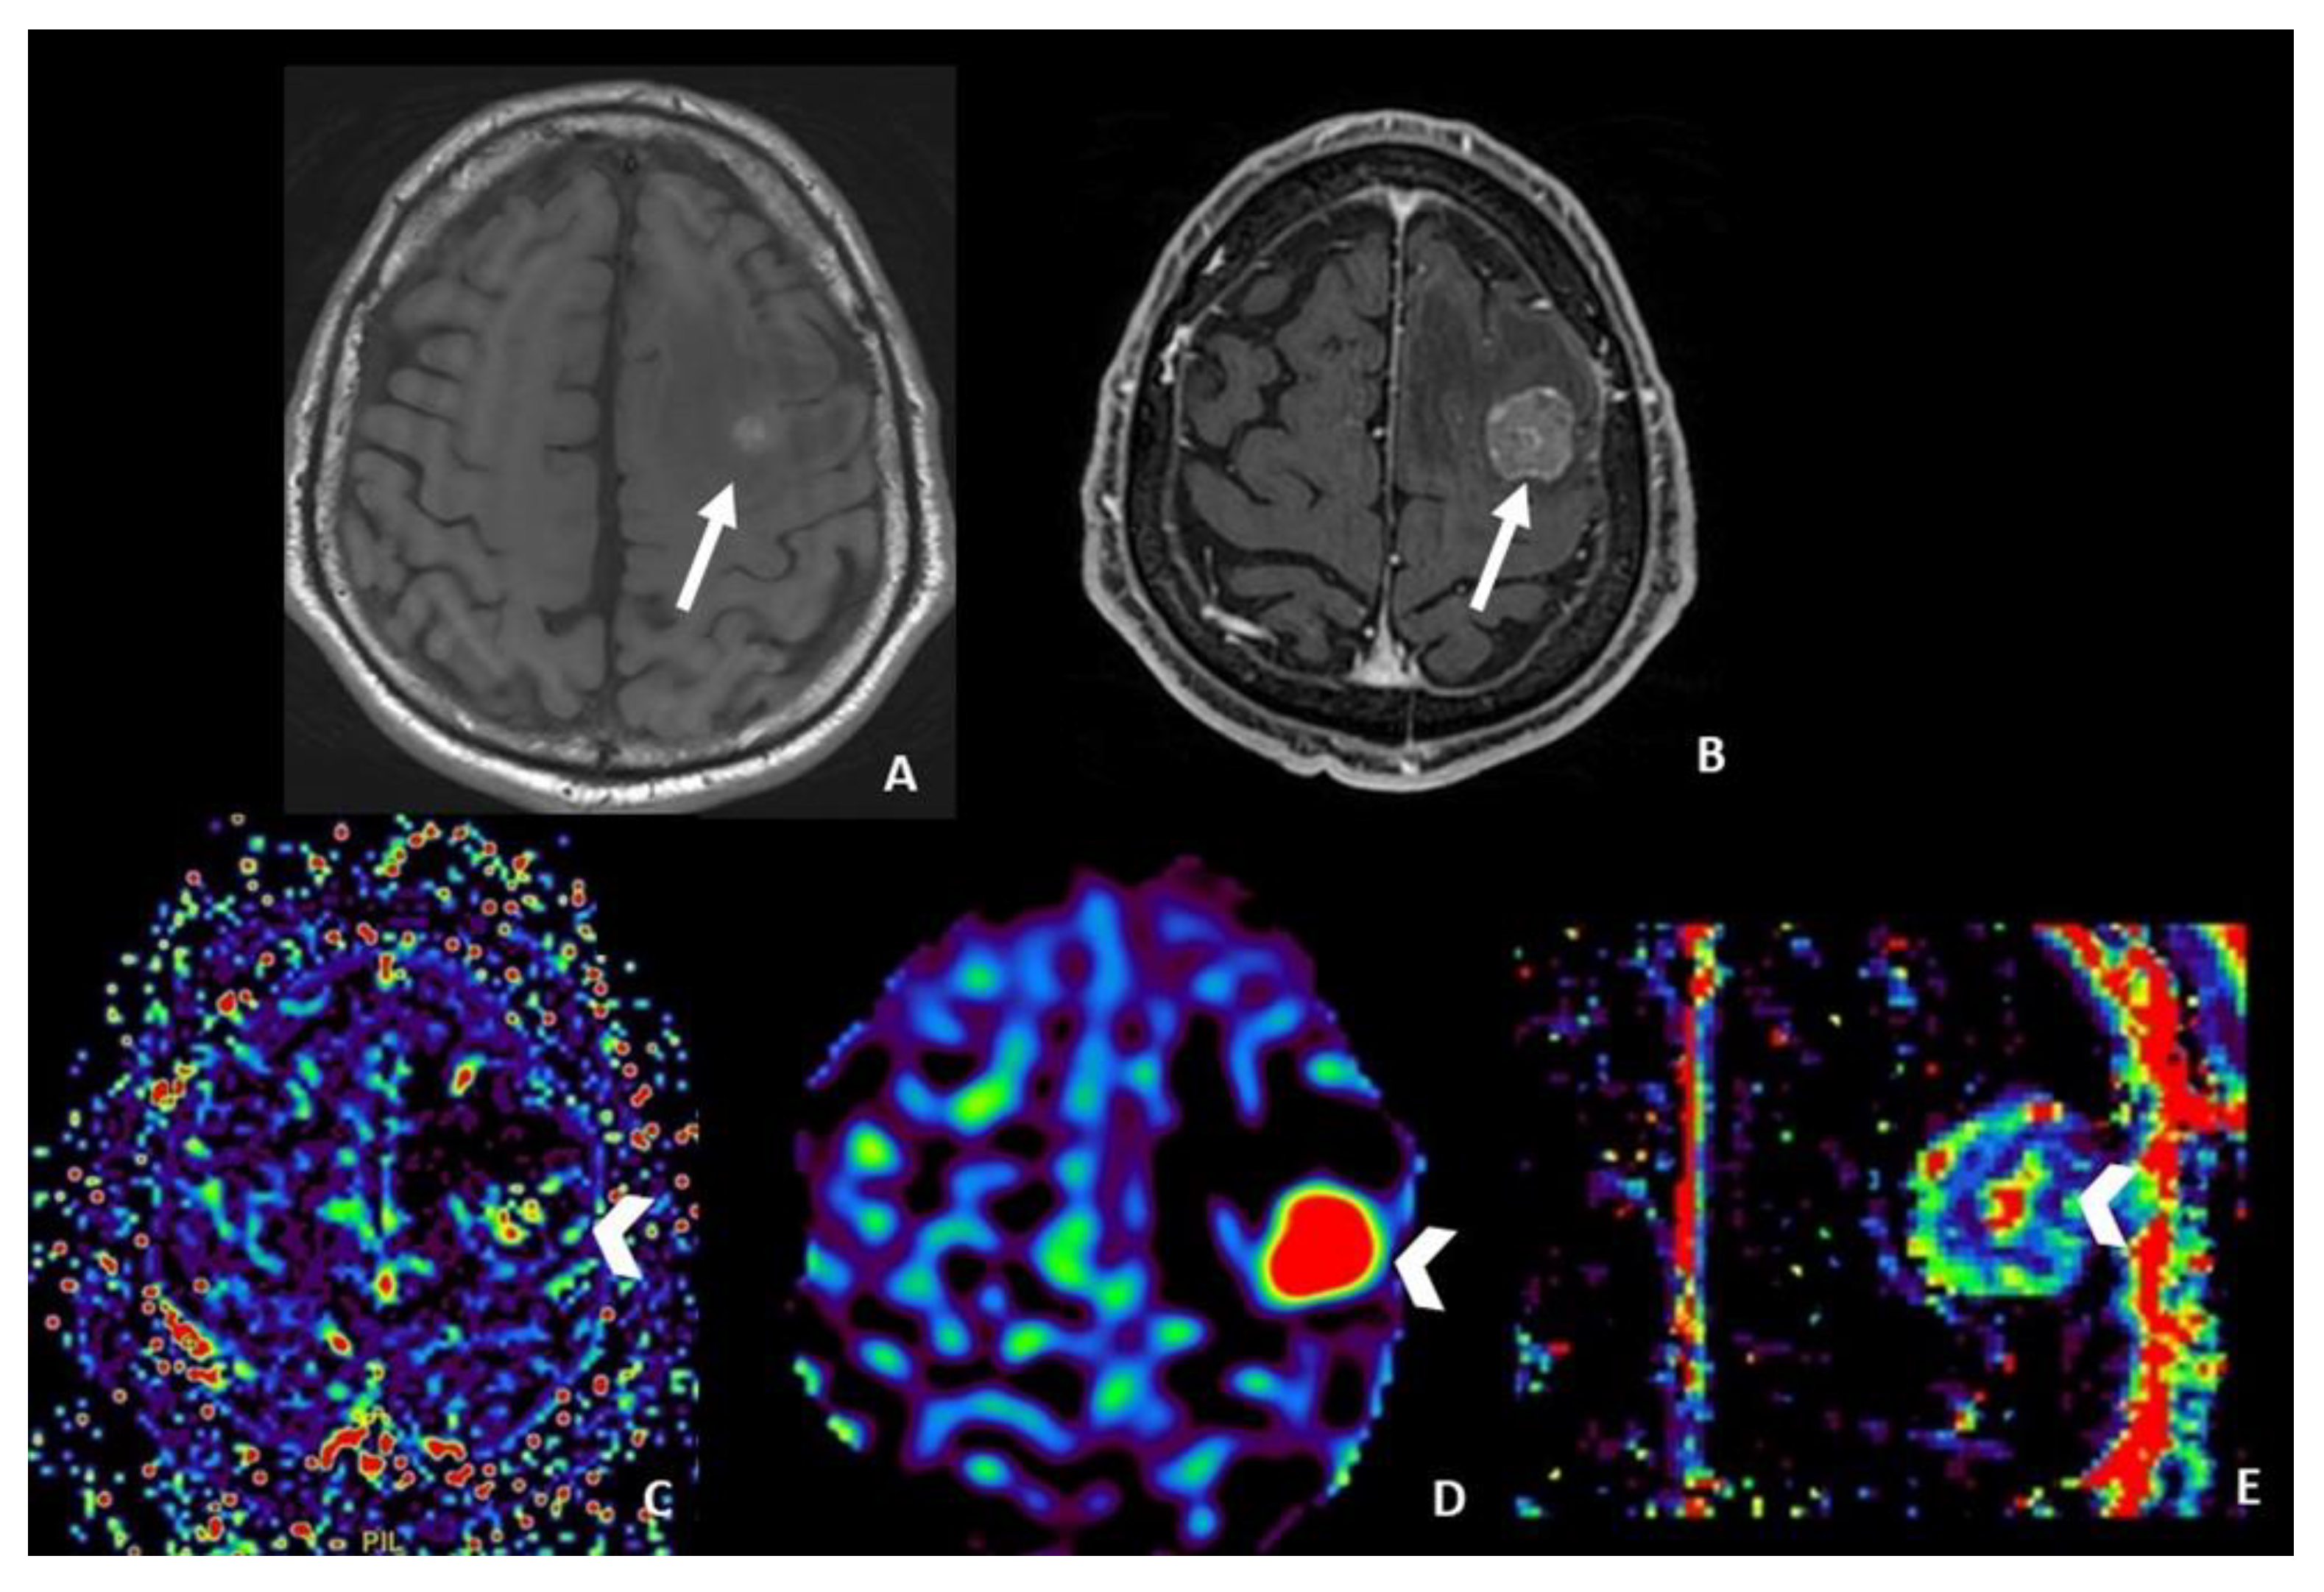

- ASL seems to be useful only in monitoring metastatic lesions characterized by high vascularity and increased CBF values, including renal cell carcinoma, melanoma and thyroid carcinoma.

4.5. Arterial Spin Labeling (ASL) Perfusion MRI

- Cicone, F.; Minniti, G.; Romano, A.; Papa, A.; Scaringi, C.; Tavanti, F.; Bozzao, A.; Maurizi Enrici, R.; Scopinaro, F. Accuracy of F-DOPA PET and Perfusion-MRI for Differentiating Radionecrotic from Progressive Brain Metastases After Radiosurgery. Eur. J. Nucl. Med. Mol. Imaging 2015, 42, 103–111. [Google Scholar] [CrossRef]

- Lai, G.; Mahadevan, A.; Hackney, D.; Warnke, P.C.; Nigim, F.; Kasper, E.; Wong, E.T.; Carter, B.S.; Chen, C.C. Diagnostic Accuracy of PET, SPECT, and Arterial Spin-Labeling in Differentiating Tumor Recurrence from Necrosis in Cerebral Metastasis after Stereotactic Radiosurgery. AJNR Am. J. Neuroradiol. 2015, 36, 2250–2255. [Google Scholar] [CrossRef]